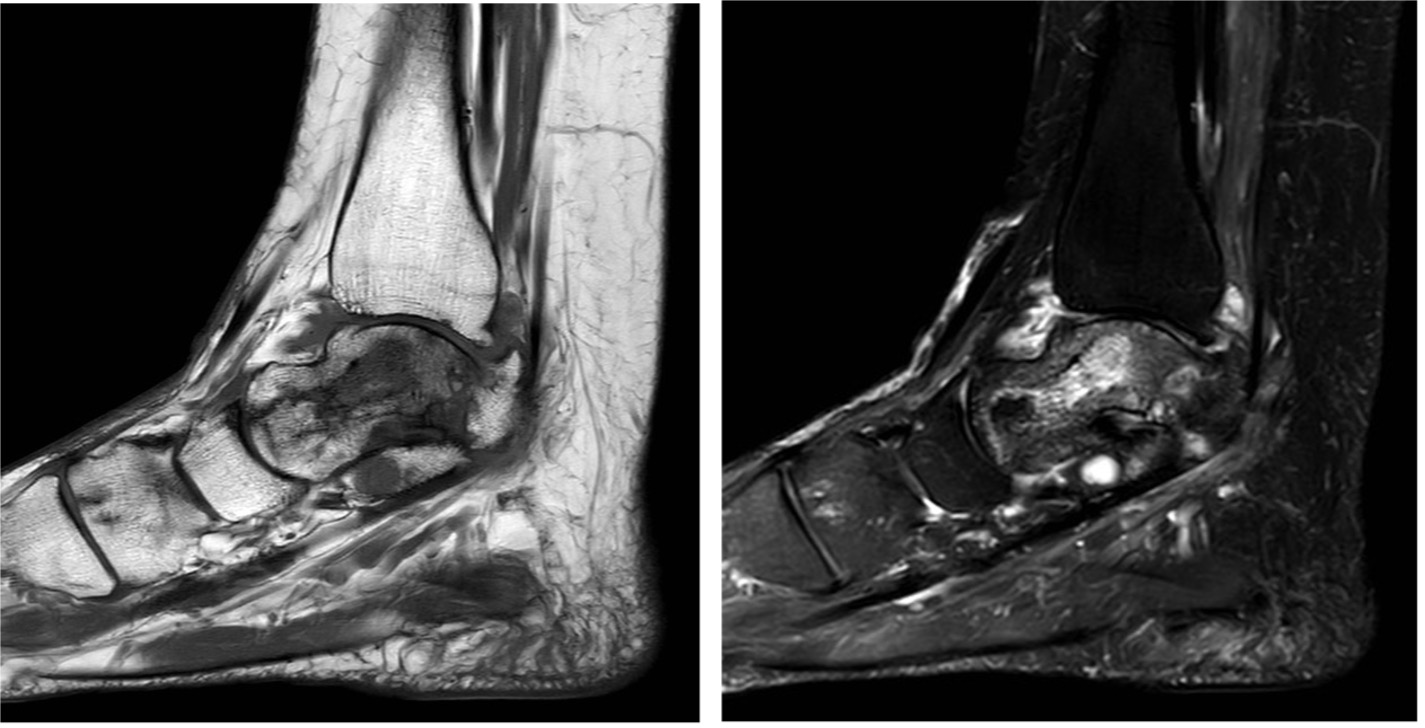

- MRI to assess disease extent, monitor progression/regression (e.g. after chemo) (Figure 16)

Figure 16: T1 and T2 MR images showing the serpiginous fracture lines on the T1 images and the patchy signal throughout the talus on the T2 images